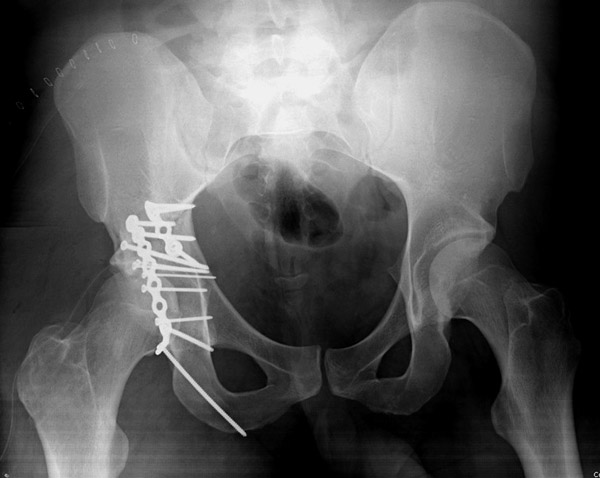

Пациент 19 лет, ДТП в сентябре 2012 г, оперирован поэтапно в др. клинике. В сентябре пациенту первым этапом была проведена операция – МОС лодыжек правой голени, МОС правой бедренной кости. Через 2 недели была проведена операция МОС костей таза и открытое устранение вывиха правого бедра.

Повторная операция – реостеосинтез костей таза была проведена через 1 месяц после первичной. Дз: задний вывих правого бедра (сроки -3 месяца). Асептический некроз головки правой бедренной кости. Неконсолидирующийся перелом средней трети правой бедренной кости, неправильно консолидирующийся перелом лодыжек правой голени с подвывихом стопы кзади, передняя медиальная нестабильность правого К/С. Сгибательно-приводящая контрактура правого Т/Б сустава, сгибательно-разгибательная контрактура правого К/С, эквинусная установка в правой стопе на фоне пост-операционного пареза

Перелом вертлужной впадины отличается от “переломов таза” не только исследованием, но также тактикой. По классификации Летурнеля расположение линии перелома характерно для поперечного перелома вертлужной впадины, но наличие шурупов в заднем крае (второй снимок) и вывих бедра подтверждают, что здесь сочетание заднего края с поперечным переломом.

Через задний доступ смогли сделать частичную репозицию, а здесь напрашивался двойной доступ спереди и сзади. Репозиция в положении на боку затруднительна, и вытяжение за перекладину над операционным столом облегчило бы репозицию.